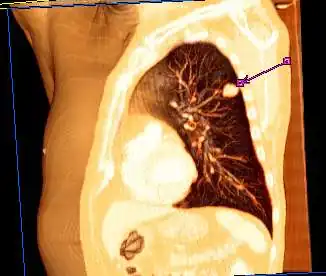

| Reconstrução em 3D de uma tomografia computadorizada de tórax mostrando um tumor no pulmão esquerdo (marcado por uma seta) | |

Os sintomas mais comuns são tosse (também a hemoptise), perda de peso e dificuldades na respiração.[7] O câncer de pulmão pode ser visto na radiografia do tórax e na tomografia computadorizada (TC). O diagnóstico é confirmado por uma biópsia, que geralmente é realizada através de uma broncoscopia ou de uma biópsia guiada por TC. O tratamento e o prognóstico dependem do tipo histológico do tumor, do estágio (grau de extensão da doença) e do bem-estar geral do paciente, medido pelo estado funcional. Os tratamentos mais comuns são a cirurgia, a quimioterapia e a radioterapia. O CNPC pode ser tratado com cirurgia, ao passo que o CPC, normalmente, responde melhor à quimioterapia e à radioterapia. Isso se dá, parcialmente, porque o CPC frequentemente se espalha muito cedo e esses tratamentos são melhores em atingir as células que já se deslocaram para outras partes do corpo.[8]

A radiografia de tórax é um dos primeiros métodos investigativos quando um paciente relata sintomas que sugerem um câncer de pulmão. Ela pode revelar uma massa óbvia, alargamento do mediastino (sugestivo de acometimento de linfonodos locais), atelectasia (colapso do alvéolo), consolidação (pneumonia) e derrame pleural.[1] A tomografia computadorizada (TC) é tipicamente utilizada para fornecer mais informações sobre o tipo e a extensão da doença. A broncoscopia ou a biópsia guiada por TC são frequentemente usadas para coletar amostras do tumor para análise histopatológica.[9]